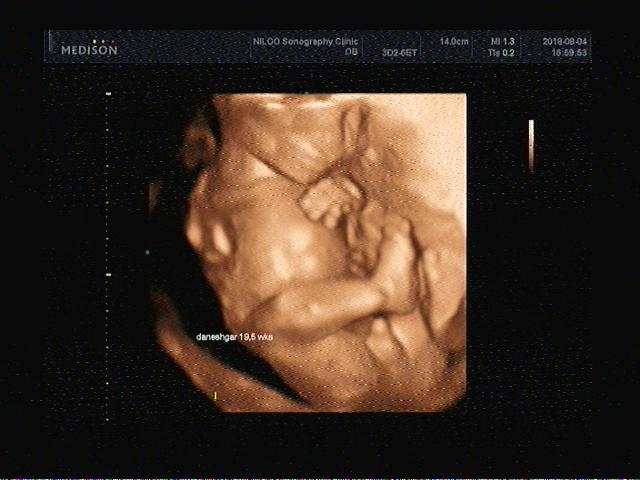

سونوگرافی بارداری در مرکز سونوگرافی نیلو

مرکز سونوگرافی نیلو

دکتر فاطمه مهتاب قربانی